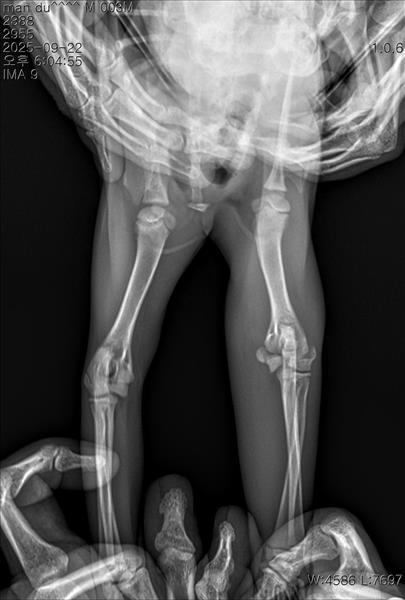

만지면 아파하길래 냅다 병원가서 엑스레이 진단을 받았어요

왼쪽 앞다리 팔꿈치 부분 성장판 골절이라고 진단을 받고 수술을 권장 받았어요..

아직 어린 우리 아이에게 이런 일이 생겨서 많이 놀라셨을 것 같아요. 말씀주신 상황과 사진을 보면 상완골 원위단, 성장판 골절이 확인됩니다.

깁스 치료는 전위가 거의 없는 "안정적" 골절에서는 가능하지만, 우리 아이의 경우 주관절의 불안정성으로 파행이 생길 수 있어 깁스만으로는 예후가 좋지 않을 듯 합니다. 깁스로 버틴다 해도 비뚤게 붙거나, 성장판 손상으로 앞다리 변형이 남을 수 있습니다.

따라서, 정확히 맞추고 고정하는 수술치료가 가장 좋은 치료 방법입니다. 나이가 어려 회복이 빠르고, 정상 보행 가능성이 높으니 수술치료를 고려해보시는 것을 권해드립니다.